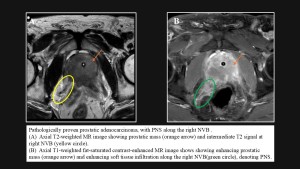

In prostatic cancer, perineural spread commonly involves the neurovascular bundle (NVB), which can be readily visualized on MRI and is considered a component of extraprostatic extension. Accurate detection of NVB involvement is critical for management, influencing decisions regarding surgery and the need for adjuvant therapies. On MRI, the NVB is located along the dorsolateral prostate and anterolateral rectum. Normally, it appears as low-signal-intensity foci within a triangular or round area of hyperintense fat at the prostate base and mid-gland on T1- and T2-weighted images. Involvement is suggested by asymmetrically enlarged nerves compared with the contralateral side, indicating tumor infiltration along the nerve sheaths.